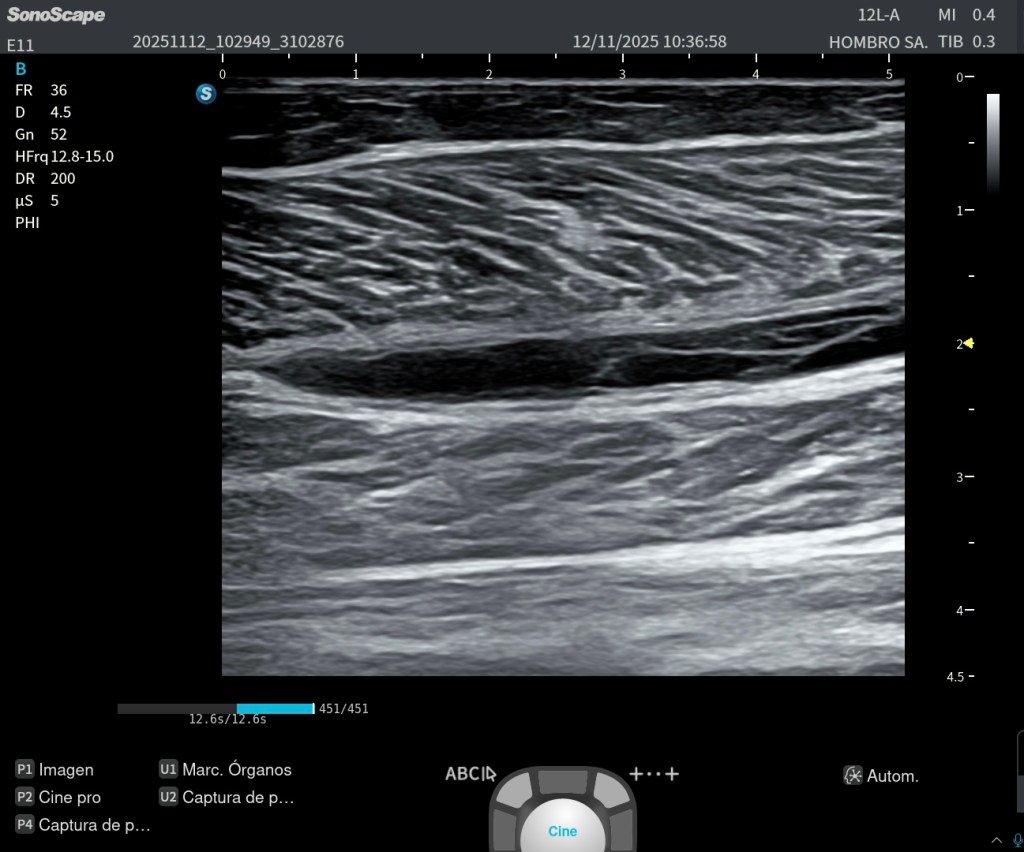

Para obtener una imagen de las raíces del plexo braquial en su salida de la columna cervical, la exploración ecográfica es técnicamente compleja. Esto se debe a que las raíces no están alineadas en un mismo plano, sino que siguen un trayecto oblicuo y escalonado desde los forámenes intervertebrales.

Por este motivo, es necesario realizar un corte sagital oblicuo, adaptado tanto a la anatomía del paciente como a las condiciones del momento de la exploración. No existe un plano único estándar: hay que buscarlo dinámicamente.

Conseguir una imagen como la de la imagen 3, donde se visualizan las raíces del plexo braquial en su salida cervical lateral, no siempre es fácil, pero tiene un gran valor docente. Esta vista permite comprender la disposición de las raíces en tres niveles:

Raíz superior (C5–C6)

Raíz media (C7)

Raíz inferior (C8–T1)

Si continuamos explorando en el eje sagital de las raíces nerviosas, progresivamente vamos a desplazarnos hacia una región donde comienzan a aparecer los músculos escalenos, que son la referencia anatómica clave en este nivel.

En este punto, es fundamental realizar una maniobra técnica importante: girar el transductor hacia un plano transversal oblicuo, adaptado al espacio interescalénico. Este ajuste nos permite visualizar de forma óptima los troncos del plexo braquial, situados entre el escaleno anterior y el escaleno medio.

Además, esta exploración no debe quedarse en una imagen estática. El estudio debe ser dinámico y continuable, permitiendo:

Seguir las raíces en plano sagital

Correlacionarlas en plano transversal

Integrarlas en el recorrido hacia los troncos del plexo braquial

Es muy importante tener un buen control de la disposición de las raíces superior, media e inferior del plexo braquial, ya que su identificación correcta condiciona toda la exploración.

En un corte axial oblicuo a nivel interescalénico, la disposición típica es la siguiente:

La raíz o tronco superior (C5–C6) suele localizarse en una posición más superficial y ligeramente lateral

La raíz o tronco medio (C7) se sitúa en una posición más central o intermedia

La raíz o tronco inferior (C8–T1) aparece en una posición más profunda y medial

👉 Es importante no confundir esta distribución: no es estrictamente anteroposterior, sino una combinación de profundidad y lateralidad.